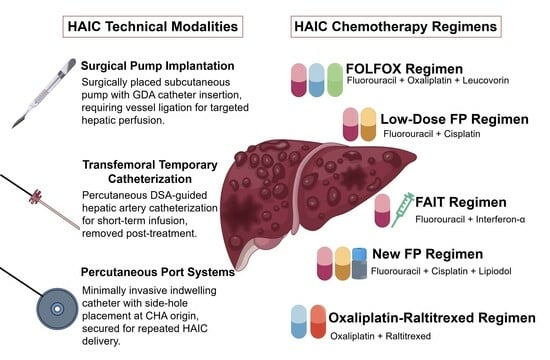

Open AccessReview

Hepatic Artery Infusion Chemotherapy for Hepatocellular Carcinoma: Clinical Advancements

Wei Xu, Qing Li and Bin Liang

Intermediate- and advanced-stage hepatocellular carcinoma (HCC) continues to present significant therapeutic challenges. Hepatic artery infusion chemotherapy (HAIC), a well-established locoregional treatment for unresectable HCC, has recently demonstrated promising clinical outcomes both as monotherapy and in combination with systemic therapies. This comprehensive review examines

[...] Read more.

Intermediate- and advanced-stage hepatocellular carcinoma (HCC) continues to present significant therapeutic challenges. Hepatic artery infusion chemotherapy (HAIC), a well-established locoregional treatment for unresectable HCC, has recently demonstrated promising clinical outcomes both as monotherapy and in combination with systemic therapies. This comprehensive review examines recent clinical advances in HAIC for HCC, with particular emphasis on evolving treatment regimens and their therapeutic efficacy.